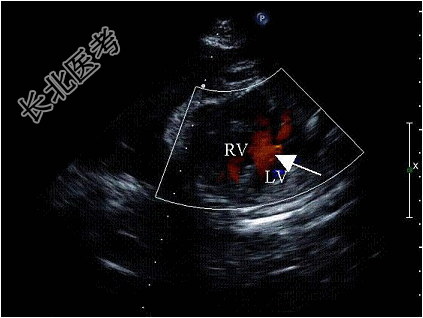

- 单项选择题孕8周时感冒,产前超声检查胎儿心脏见图, 最可能诊断为( )

A、室间隔缺损

B、房间隔缺损

C、大动脉转位

D、单心室

E、正常心脏